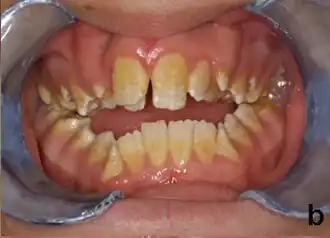

La amelogenesis imperfecta es una enfermedad genética que se presenta con formación anormal del esmalte o capa externa de los dientes. El esmalte está compuesto principalmente por mineral, que es formado y regulado por las proteínas en él. La amelogenesis imperfecta es debida al mal funcionamiento de las proteínas en el esmalte: ameloblastina, enamelina, tuftelina y amelogenina.

Las personas afectadas con amelogenesis imperfecta tienen dientes con color anormal: amarillo, marrón o gris. Los dientes tienen un mayor riesgo de sufrir cavidades dentales y son hipersensitivos a los cambios de temperatura. Este desorden puede afectar cualquier número de dientes.

Las mutaciones en algunos de estos genes alteran la estructura de estas proteínas o incluso impiden a los genes producir por completo las proteínas. Como resultado el esmalte dental es anormalmente fino o suave y puede tener un color amarillo o marrón. Los dientes con esmalte defectuoso son débiles y fácilmente dañados.